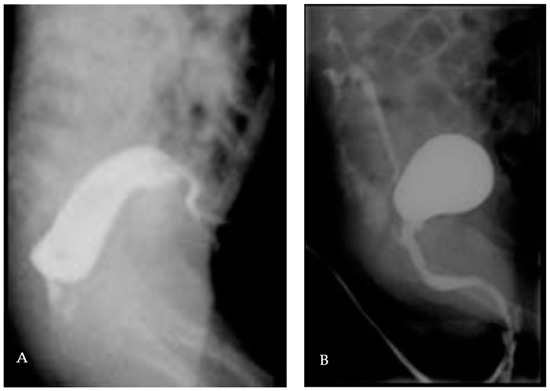

A premature boy (33 weeks of gestation) was diagnosed at birth with a syndromic anorectal malformation. After performing a separate, double-barrelled left colostomy, the further diagnostic workup showed a recto-prostatic fistula (high anorectal malformation, Figure 7A), sacral agenesis, a sacral meningocele, left renal agenesis associated with cysticseminal vesicles, a vesicoureteral reflux grade III right (Figure 7B), an inguinal testis left, and microcephaly. The genetic results are still pending.

Figure 7. (A): Colon contrast imaging with recto-prostatic fistula. (B): MCUG with recto-prostatic fistula and vesicoureteral reflux grade III right.